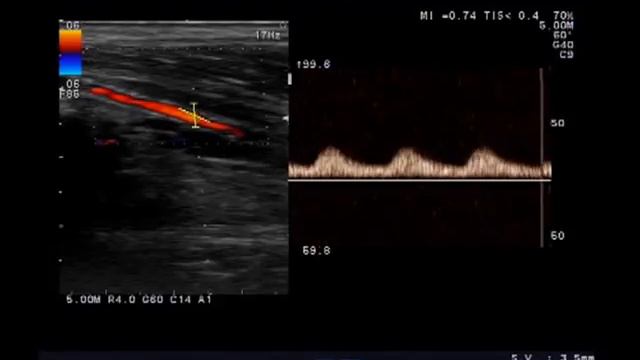

Стенки ПББА с гиперэхогенными включениями, кровоток коллатеральный

Перейти к лекции https://medprinting.ru/lekciya-3-ultrazvukovoe-issledovanie-arterij-...